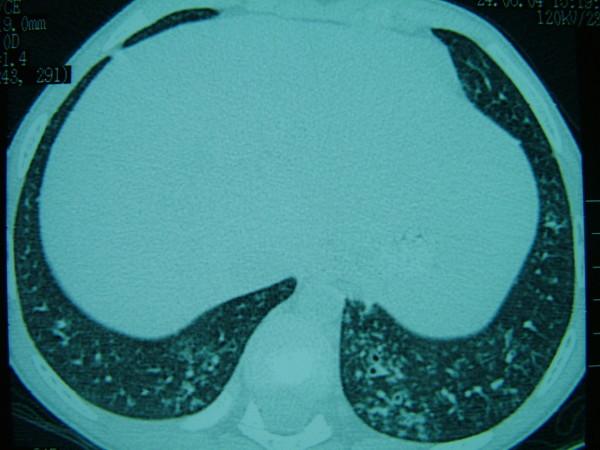

We present a 6-year-old girl with yellow nail syndrome having pansinusitis and bronchiectasis.

我们报告一名6岁患黄甲综合征的女孩,伴有全鼻窦炎和支气管扩张。